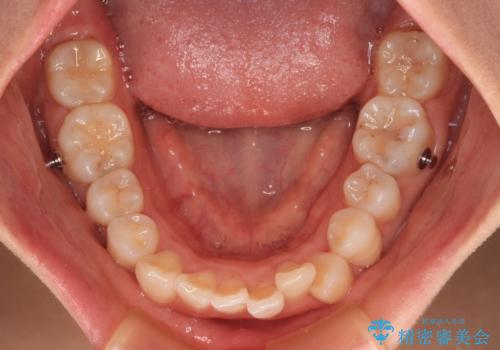

- 上下前歯のデコボコを改善したいとのことで来院された患者様です。

マウスピースを長時間装着し続ける自信はあまりないとのことでしたが、目立たない装置であれば頑張って装着するとのことで、インビザラインによる矯正治療を行うこととしました。

初めの1年くらいは何とか頑張って装着してくださいましたが、途中から変化をあまり感じられなくなり、日々の装着時間は徐々に短くなってしまいました。

前歯のデコボコはもっと改善できましたが、3年半が経過し、初診時と比べたら大幅に良くなったとのことで終了することとなりました。